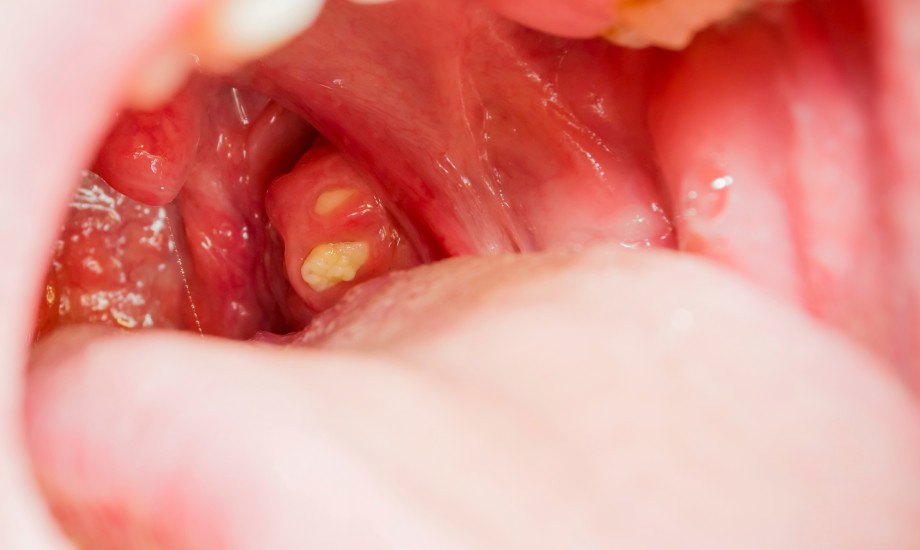

Tonsillen-OP: Intrakapsuläre Technik senkt Schmerzbelastung

Die operative Entfernung der Gaumenmandeln ist bei Jugendlichen und Erwachsenen nicht selten mit erheblicher postoperativer Morbidität verbunden. Eine randomisierte Studie aus Finnland hat nun untersucht, ob moderne intrakapsuläre Verfahren die Erholungszeit verkürzen.